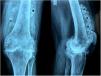

A 55-year-old lady presented in the outpatient clinic, with the complaints of mechanical knee pain of three-year duration. Radiographs (Fig. 1) of the knee were suggestive of multiple loose radio-opaque calcified bodies around the knee joint.

The radiographs are pathognomonic of Synovial Osteochondromatosis, an atypical neoplastic disease, with an occurrence rate of 1 in 100,000 people.1 People are likely to get affected by Synovial Osteochondromatosis in their 3rd to 5th decades of life, occurs almost 2 times more frequently in men than women. The pathogenesis includes hyperplastic metaplasia of connective tissue where hyaline cartilage gets calcified into multiple intra-articular loose bodies in synovial tissues, within the joint, bursa or tendon sheaths. Though knee is mostly affected, hip, shoulder, ankle, elbow, and wrist joints can also be affected. Joint swelling and tenderness, locking, pain, restrictions of range of motion in affected joints are some common clinical features. This disease has potential to transform into chondrosarcoma, in very few cases.2 Surgical excision of the chondromal nodules and synovectomy are the mainstay of treatment to prevent late degenerative transformation. Overall with a reported recurrence of 3–60% in primary disease, the recurrence rate goes below 10% after surgery.1,2